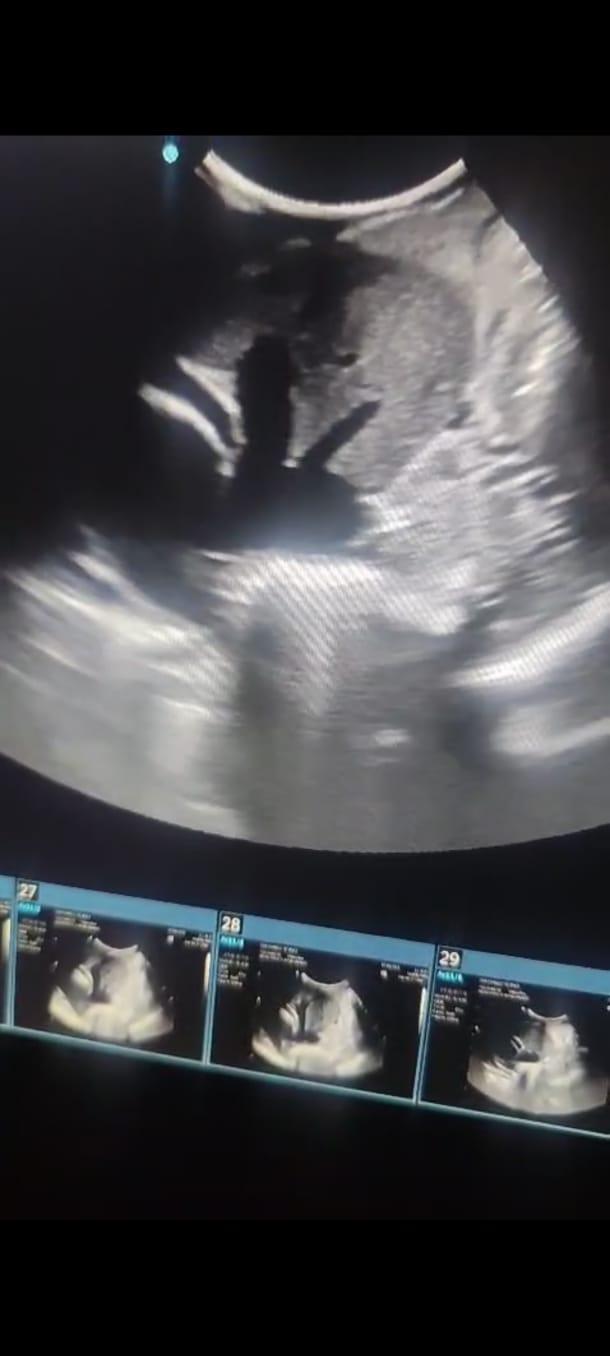

Gestação e acompanhamento fetal

A ultrassonografia veterinária é um exame de imagem essencial para diagnósticos precisos e minimamente invasivos. Na nossa clínica, contamos com equipamentos modernos e profissionais capacitados para oferecer um exame seguro, rápido e com alta qualidade.